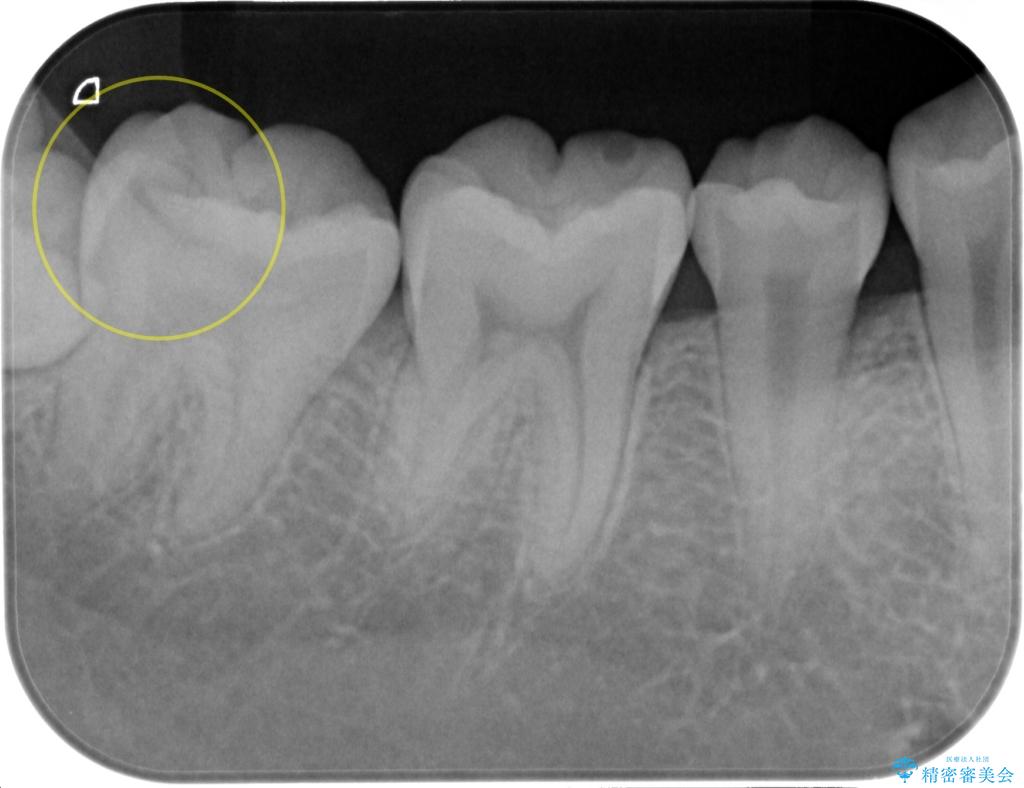

- 検査の結果虫歯が見つかった患者様です。

親知らずを抜歯してから虫歯を除去した後、ゴールドの詰め物で修復します。

比較的大きな虫歯でしたがゴールドでの修復にすることで歯の削る量を抑え、精度の高い治療を行うことができました。

親知らずの問題も同時に解決することで今後の虫歯リスクを抑えています。